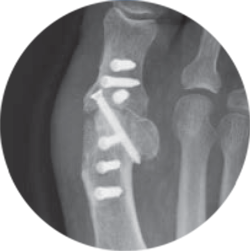

colink pcr product and xrays

Since the plates are invisible on X-ray, with Barium sulfate added for slight visibility, experience radiolucent artifact-free imaging.

Invisible on X-ray, so you can see more of the bone